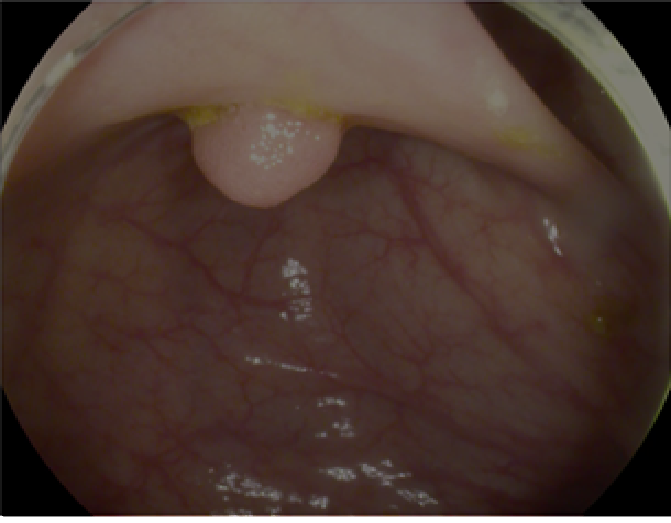

The study used a publicly available dataset of polyp-frames obtained from the ETIS-Larib database [34], containing 196 polyp images. These images were obtained from 34 different colonoscopy videos of 44 different polyps with various appearances and sizes, having a resolution of pixels. The ground truth of polyp areas for polyp datasets is determined by expert video endoscopists. A CNN model trained with such a small amount of data is likely to be meaningless and unstable, so data augmentation was performed on the polyp dataset. Data augmentation had to be performed on the colonoscopy images by considering vivid variations. Otherwise over-fitting would have occurred. In a colonoscopy imagery, polyps exhibits large variations in location, color, and scale. Moreover, variations in brightness and definition also occur due varrying the view-point of the camera. Therefore, in addition to photometric distortions and geometric distortions, we also have considered zooming, shearing, and altering brightness as strategies for data augmentation.

For photometric distortions, we controlled brightness and contrast as an enhancement, while blurring by adding noise with a standard deviation of 1.0. Similarly, for geometric distortions, clock-wise rotation of the polyp images with angles of , , and were performed. Zoom-in and zoom-out with zooming parameters such as 30.00% and 10.00% were performed to obtain different scales of polyp images. Lastly, shearing for both the x-axis and the y-axis was performed to shear the images from left to right and top to bottom, respectively. Fig. 4 shows photometric and geometric forms of image augmentation. In this way, we augmented the data set of the ETIS-Larib database from 196 polyp images to 2,156 images, which is more suitable for training the proposed deep CNN model.

The results shown in Fig. 6 are generated using the proposed deep CNN model on the augmented data set. It can be observed that the proposed model shows better polyp detection performance. As illustrated in Fig. 6, polyps within a frame can be identified at multiple positions, and as noted above in this case, the TP for detection is considered to be 1. The proposed deep CNN model performed better than other benchmark results in terms of the performance metrics listed above, as shown in Table. 2 and Fig. 6.